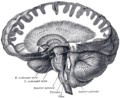

صور اضافية

Computed tomography of head, with cerebellum visible at lower part